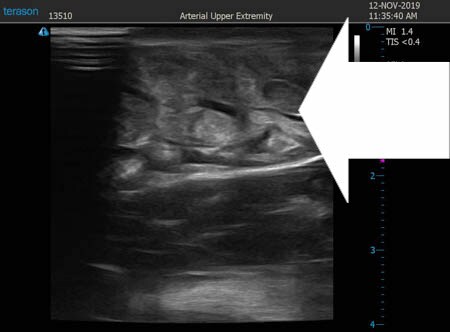

いつものように3Dタッチビュー(超音波)で

皮下脂肪層を評価してみましょう。

右二の腕

↓ ↓ ↓

上の画像の部分の皮下脂肪層をつまんでみましょう。